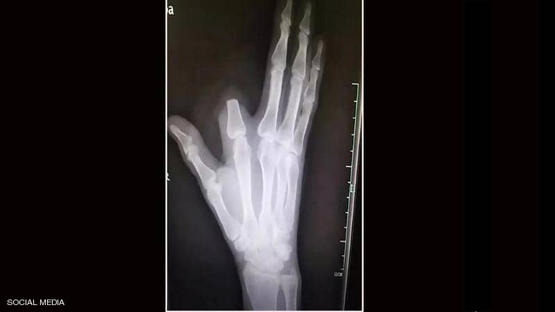

وظن الرجل أن لدغة الأفعى شديدة السمية وقد تؤدي إلى موته فورا، فسارع إلى قطع إصبعه بسكين كان بحوزته من أجل "إنقاذ حياته"، بحسب ما أوردت شبكة "فوكس نيوز".

لكن الرجل الذي اتخذ القرار المؤلم بقطع إصبعه، لم يكن مضطرا لفعل ذلك، لأن سم هذا النوع من الأفاعي ليس قاتلا على الإطلاق، بل إنه يستخدم في تحضير علاجات للمفاصل والعظام.